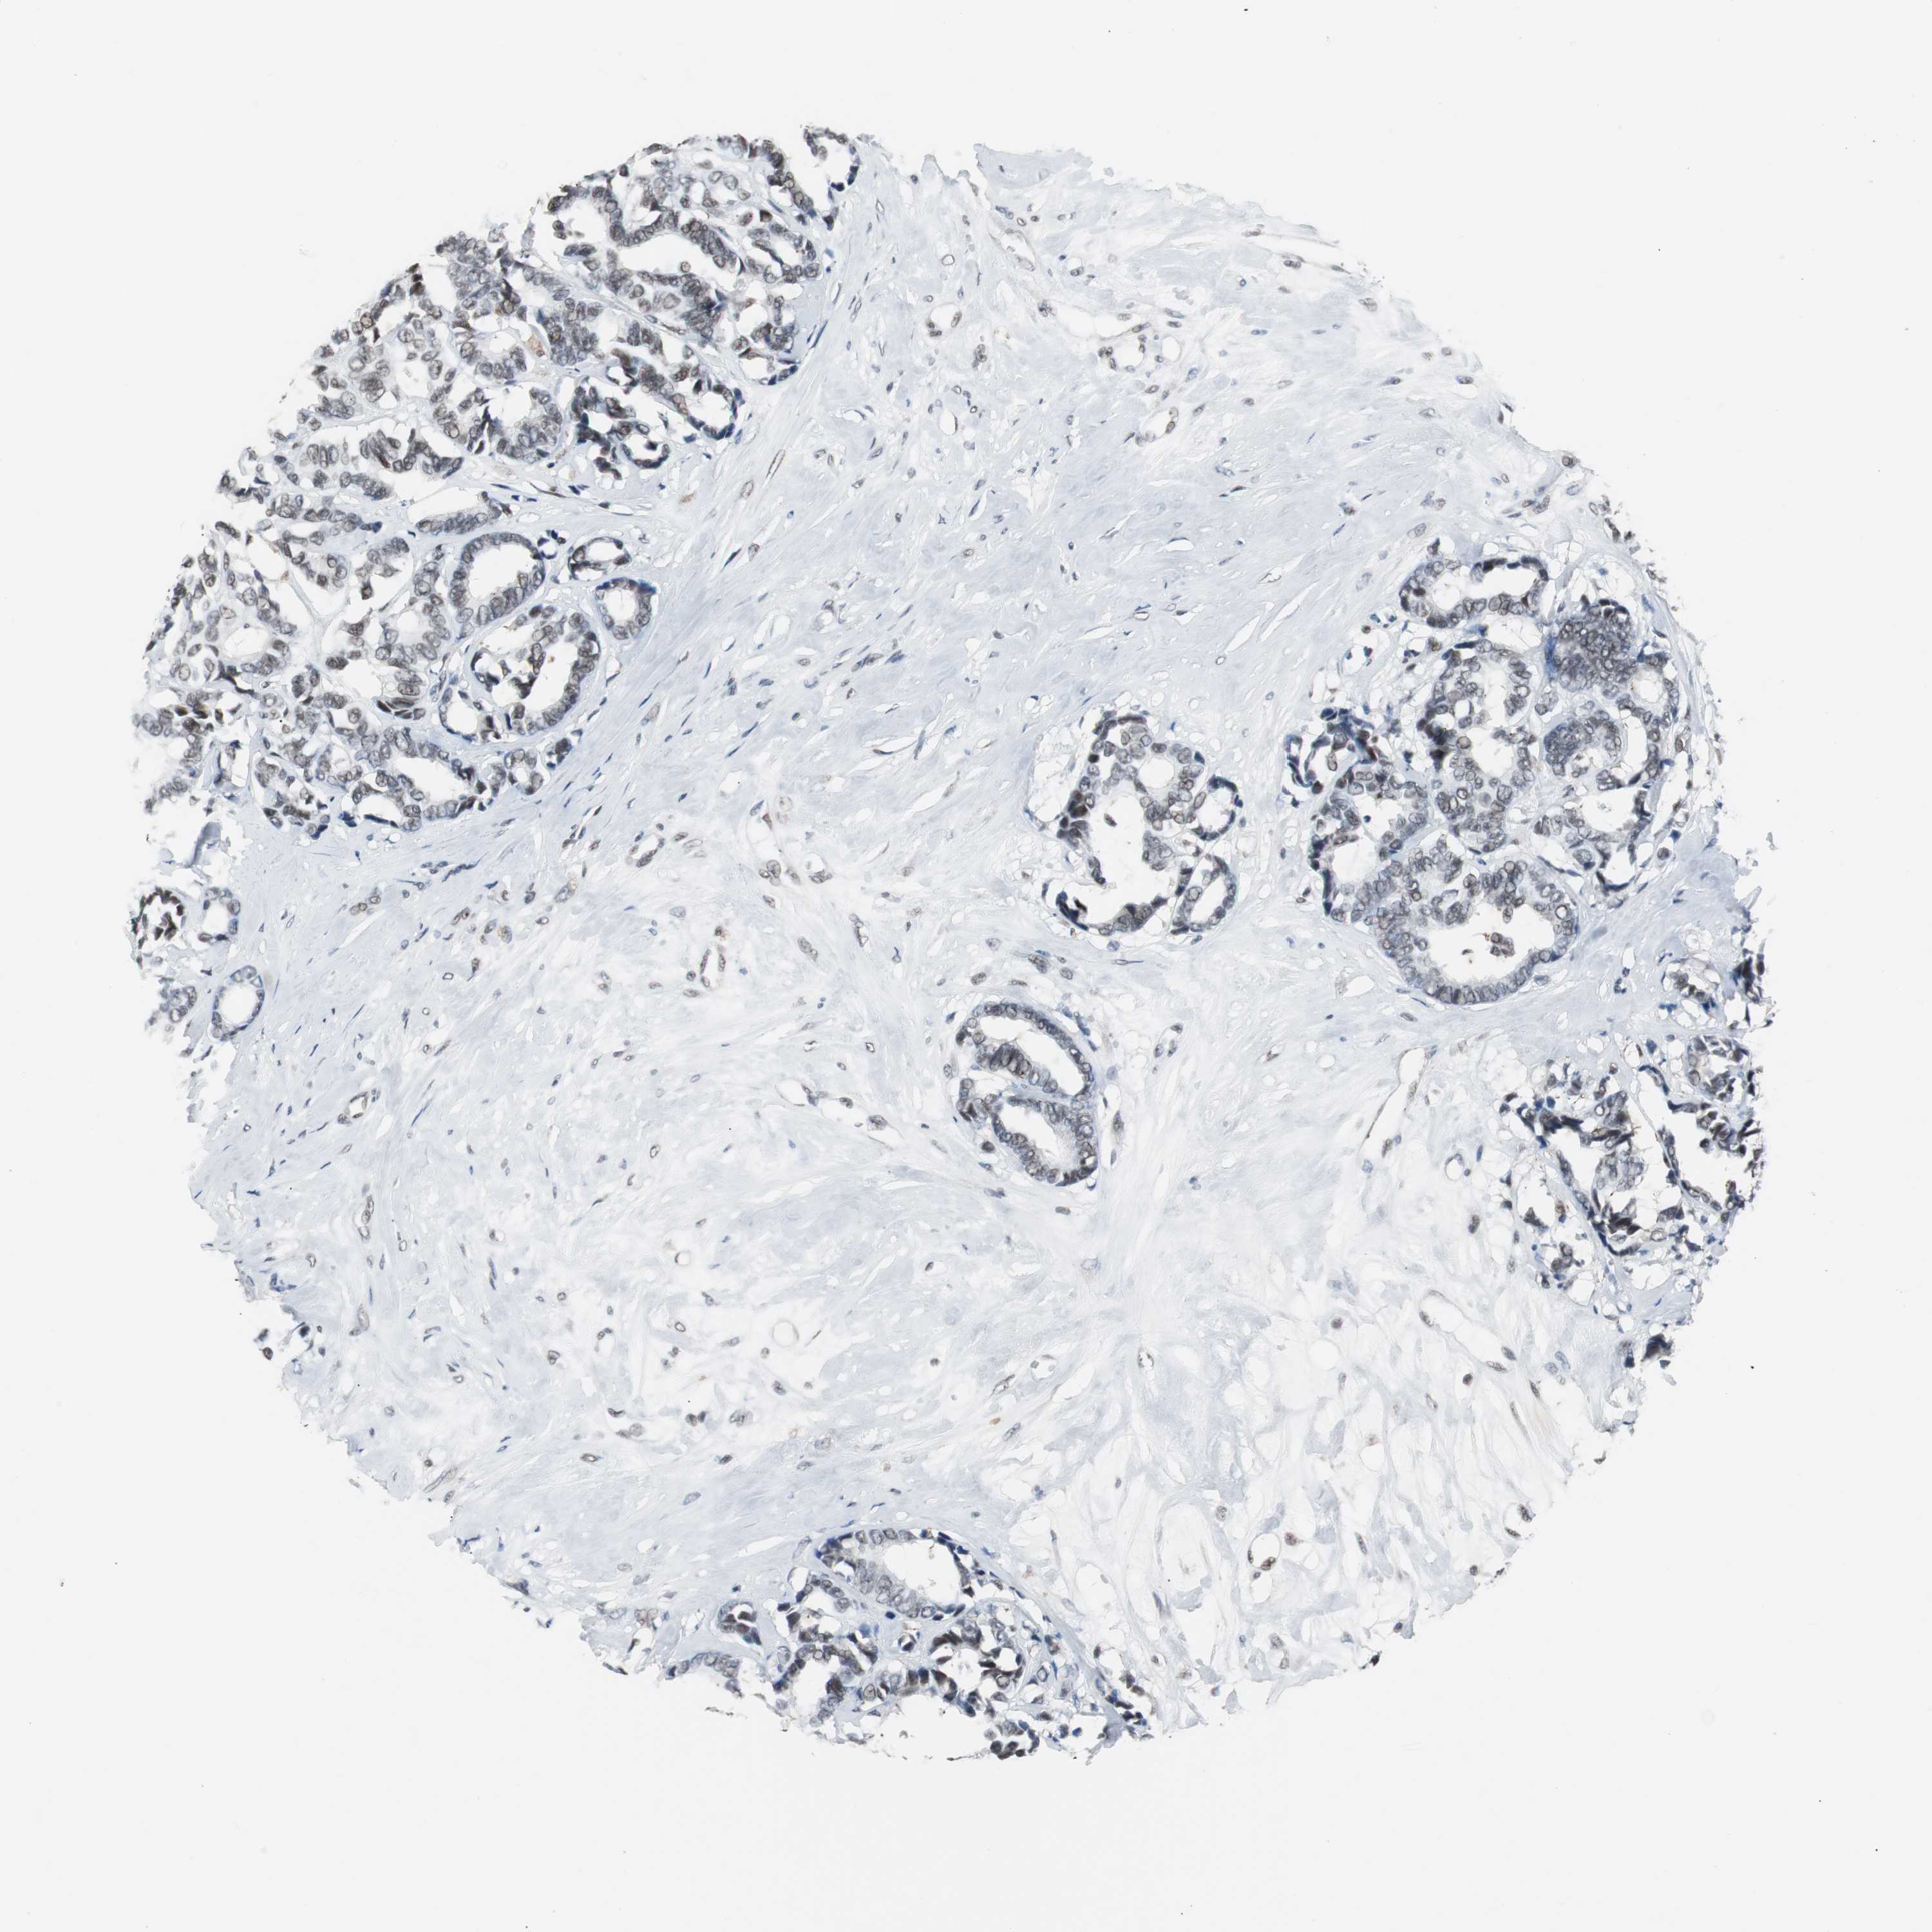

CANCER BREAST CANCER Show tissue menu

BRCA TCGA BRCA VALIDATION PROTEIN EXPRESSION